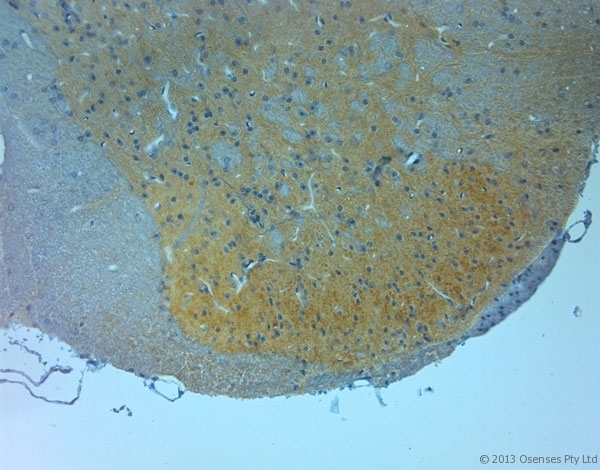

- Rabbit antibody to NMDAR3A (990-1040). IHC on paraffin sections of rat spinal cord tissue using Rabbit antibody to NMDAR3A (990-1040). HIER: 1 mM EDTA, pH 8 for 20 min using Thermo PT Module. Blocking: 0.2% LFDM in TBST filtered through a 0.2 micron filter. Detection was done using Novolink HRP polymer from Leica following manufacturer's instructions. Primary antibody: dilution 1:1000, incubated 30 min at RT (using Autostainer). Sections were counterstained with Harris Hematoxylin.